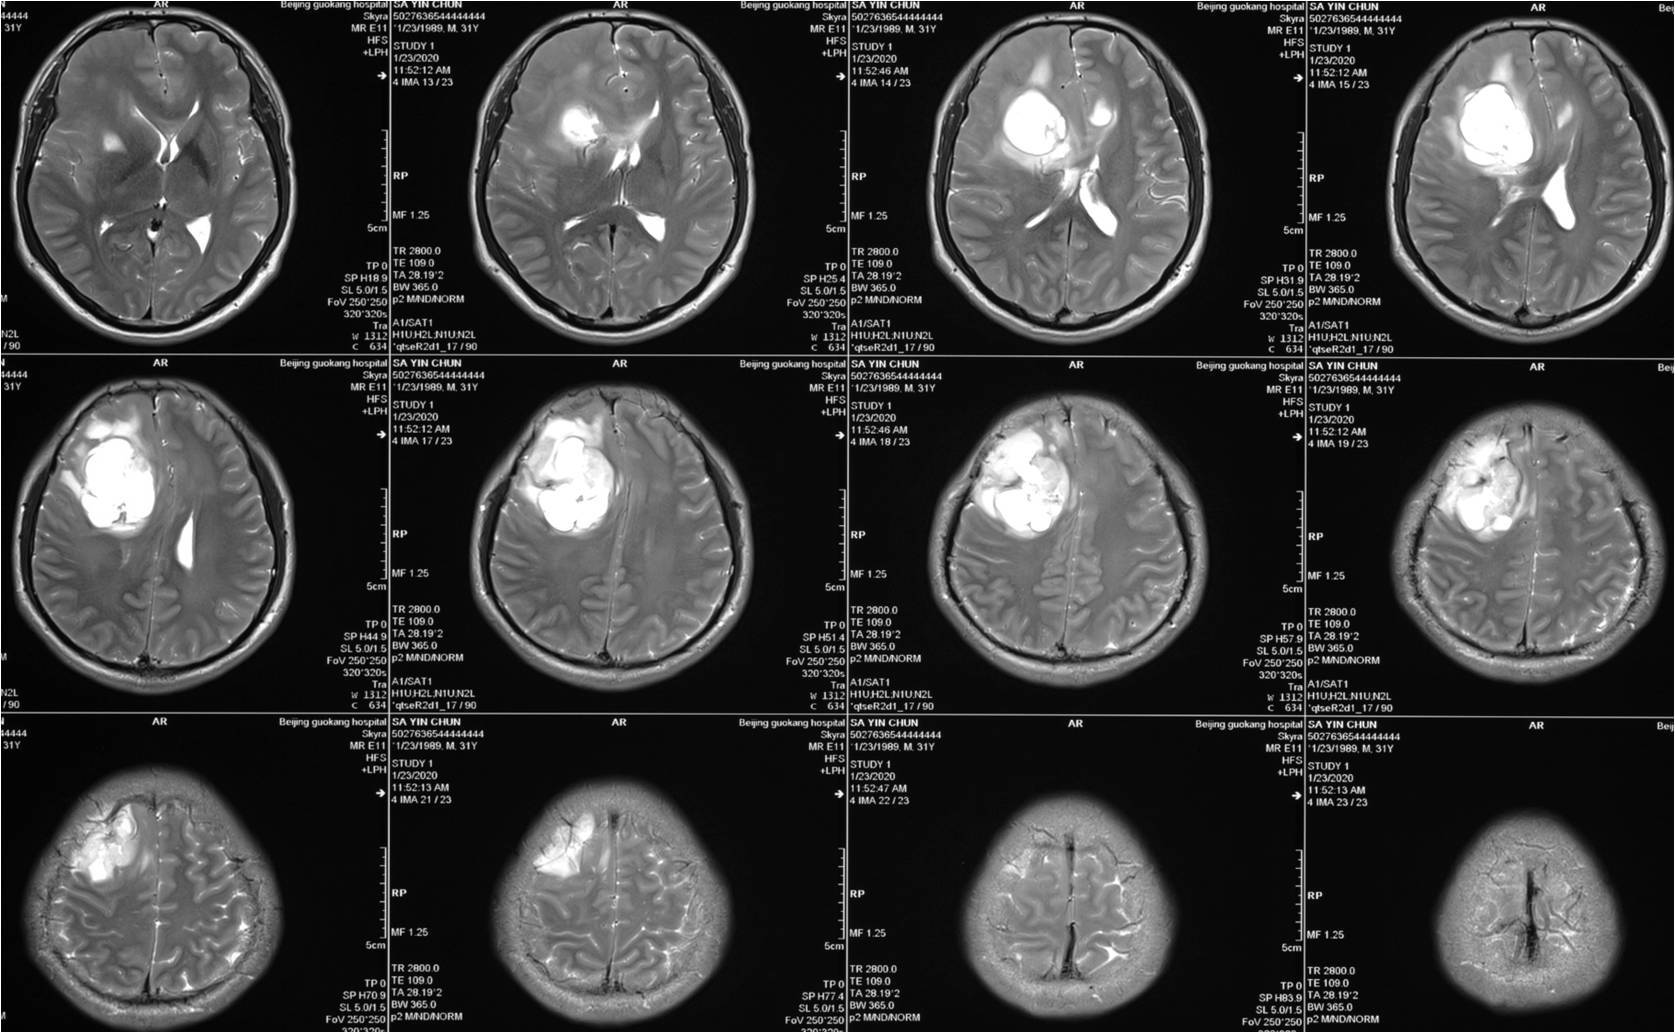

上皮样胶质母细胞瘤一例(2018华东胶质瘤mdt病例二)--浙二神外周刊(第

高级别胶质瘤的那些事(省中神外病例分享 第11期)

「病例快讯」——(第8期):肿瘤三组之高级别胶质瘤系列